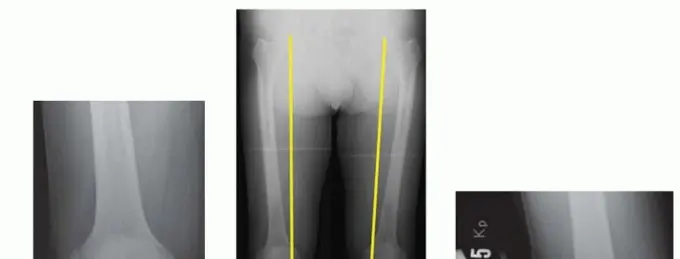

صورة 1: أشعة سينية قبل العملية. أ. أشعة سينية أمامية خلفية للركبة اليمنى تظهر تضييقًا كبيرًا في المسافة المفصلية الإنسية مع تكوّن نتوءات عظمية.

صورة 2: أشعة سينية قبل العملية. ب. منظر المحور الميكانيكي للأطراف السفلية يظهر انحرافًا (تقوسًا) ثنائيًا في الطرف السفلي.

- الأشعة السينية الطويلة للطرف السفلي (Mechanical Axis View): توفر هذه الأشعة محاذاة دقيقة للطرف السفلي بالكامل. تُستخدم هذه الرؤية بشكل شائع في التخطيط قبل الجراحة لـ HTO (الصورة 1 ب).

- أشعة الإجهاد (Varus or Valgus Stress Views): تساعد في تصور استقرار التراخي الإنسي والوحشي في خشونة الركبة الإنسية والتأكد من أن الجزء الوحشي سليم تقريبًا (الصورة 1 ج).